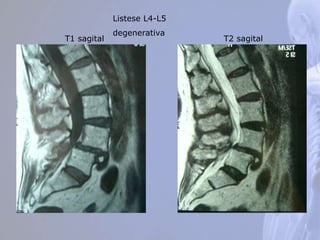

T1 sagital T2 sagital

Listese L4-L5

degenerativa

T1 sagital T2sagital Listese L4-L5 degenerativa